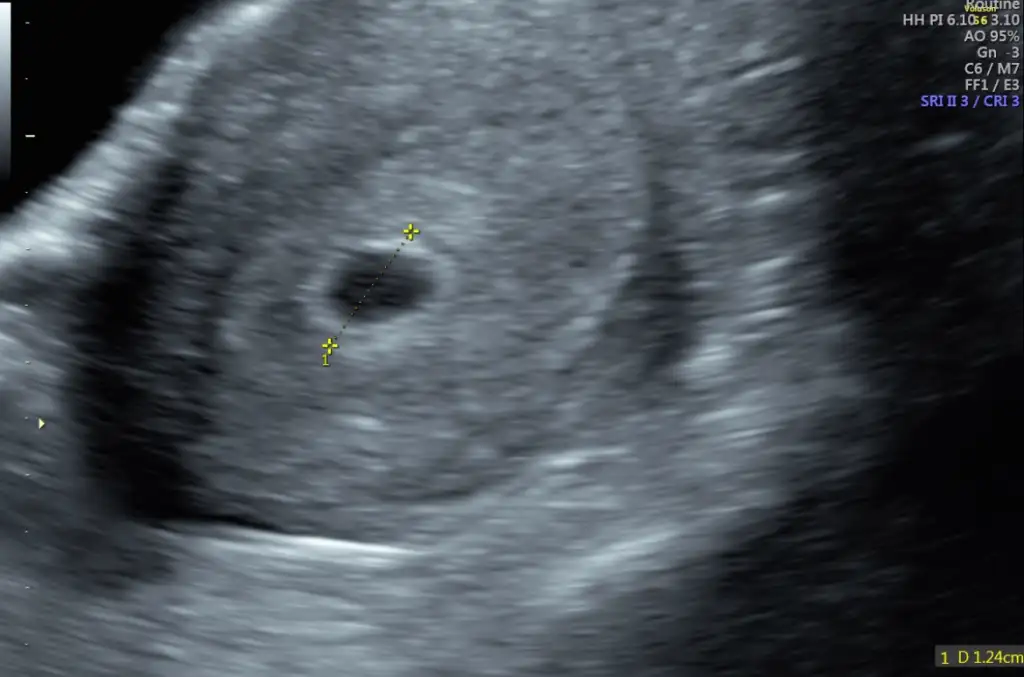

Canım bu benim 5+4 kese görüntüm, boş görünüyor. Neden bu kadar erkenden boş gebelik olabilir demiş anlamadım. Sonra 6+5’te gittiğimde bebeği de gördük kalp atışını da duyduk. İnşallah senin de öyle olur, bu haftada böyle olması bence çok normal.20 mm gözüküyor kese, bu saatten sonra gözükür mü acaba bugun 5+6 olmuşum

İnşallah öyledir. Aslında doktor gebelik kesen, yolk kesen çok güzel dedi. Doppler için başka yere gönderdi beni. Göndermesinin sebebi de kalp atışlarını duyacaksın büyük ihtimal diye. Radyoloji uzmanı böyle bir şey söyleyince bir an şok yaşadım. Ne olduğumu şaşırdımCanım bu benim 5+4 kese görüntüm, boş görünüyor. Neden bu kadar erkenden boş gebelik olabilir demiş anlamadım. Sonra 6+5’te gittiğimde bebeği de gördük kalp atışını da duyduk. İnşallah senin de öyle olur, bu haftada böyle olması bence çok normal.Eki Görüntüle 3603775

Neden stres yaptınız?Kese falan kaç mm boyutundaydı hatırlıyor musunuz, stresimden Ölücem radyoloji uzmanı nasıl böyle bir yorum yapabilir ki aklım almıyor benim kesem 20 mm, yolk kesesi de 3 mm

Kese 25 e kadar beklenir 25 mm olunca kese bebek görünmesse boş gebelik şüphesi olabilir ancakKese falan kaç mm boyutundaydı hatırlıyor musunuz, stresimden Ölücem radyoloji uzmanı nasıl böyle bir yorum yapabilir ki aklım almıyor benim kesem 20 mm, yolk kesesi de 3 mm